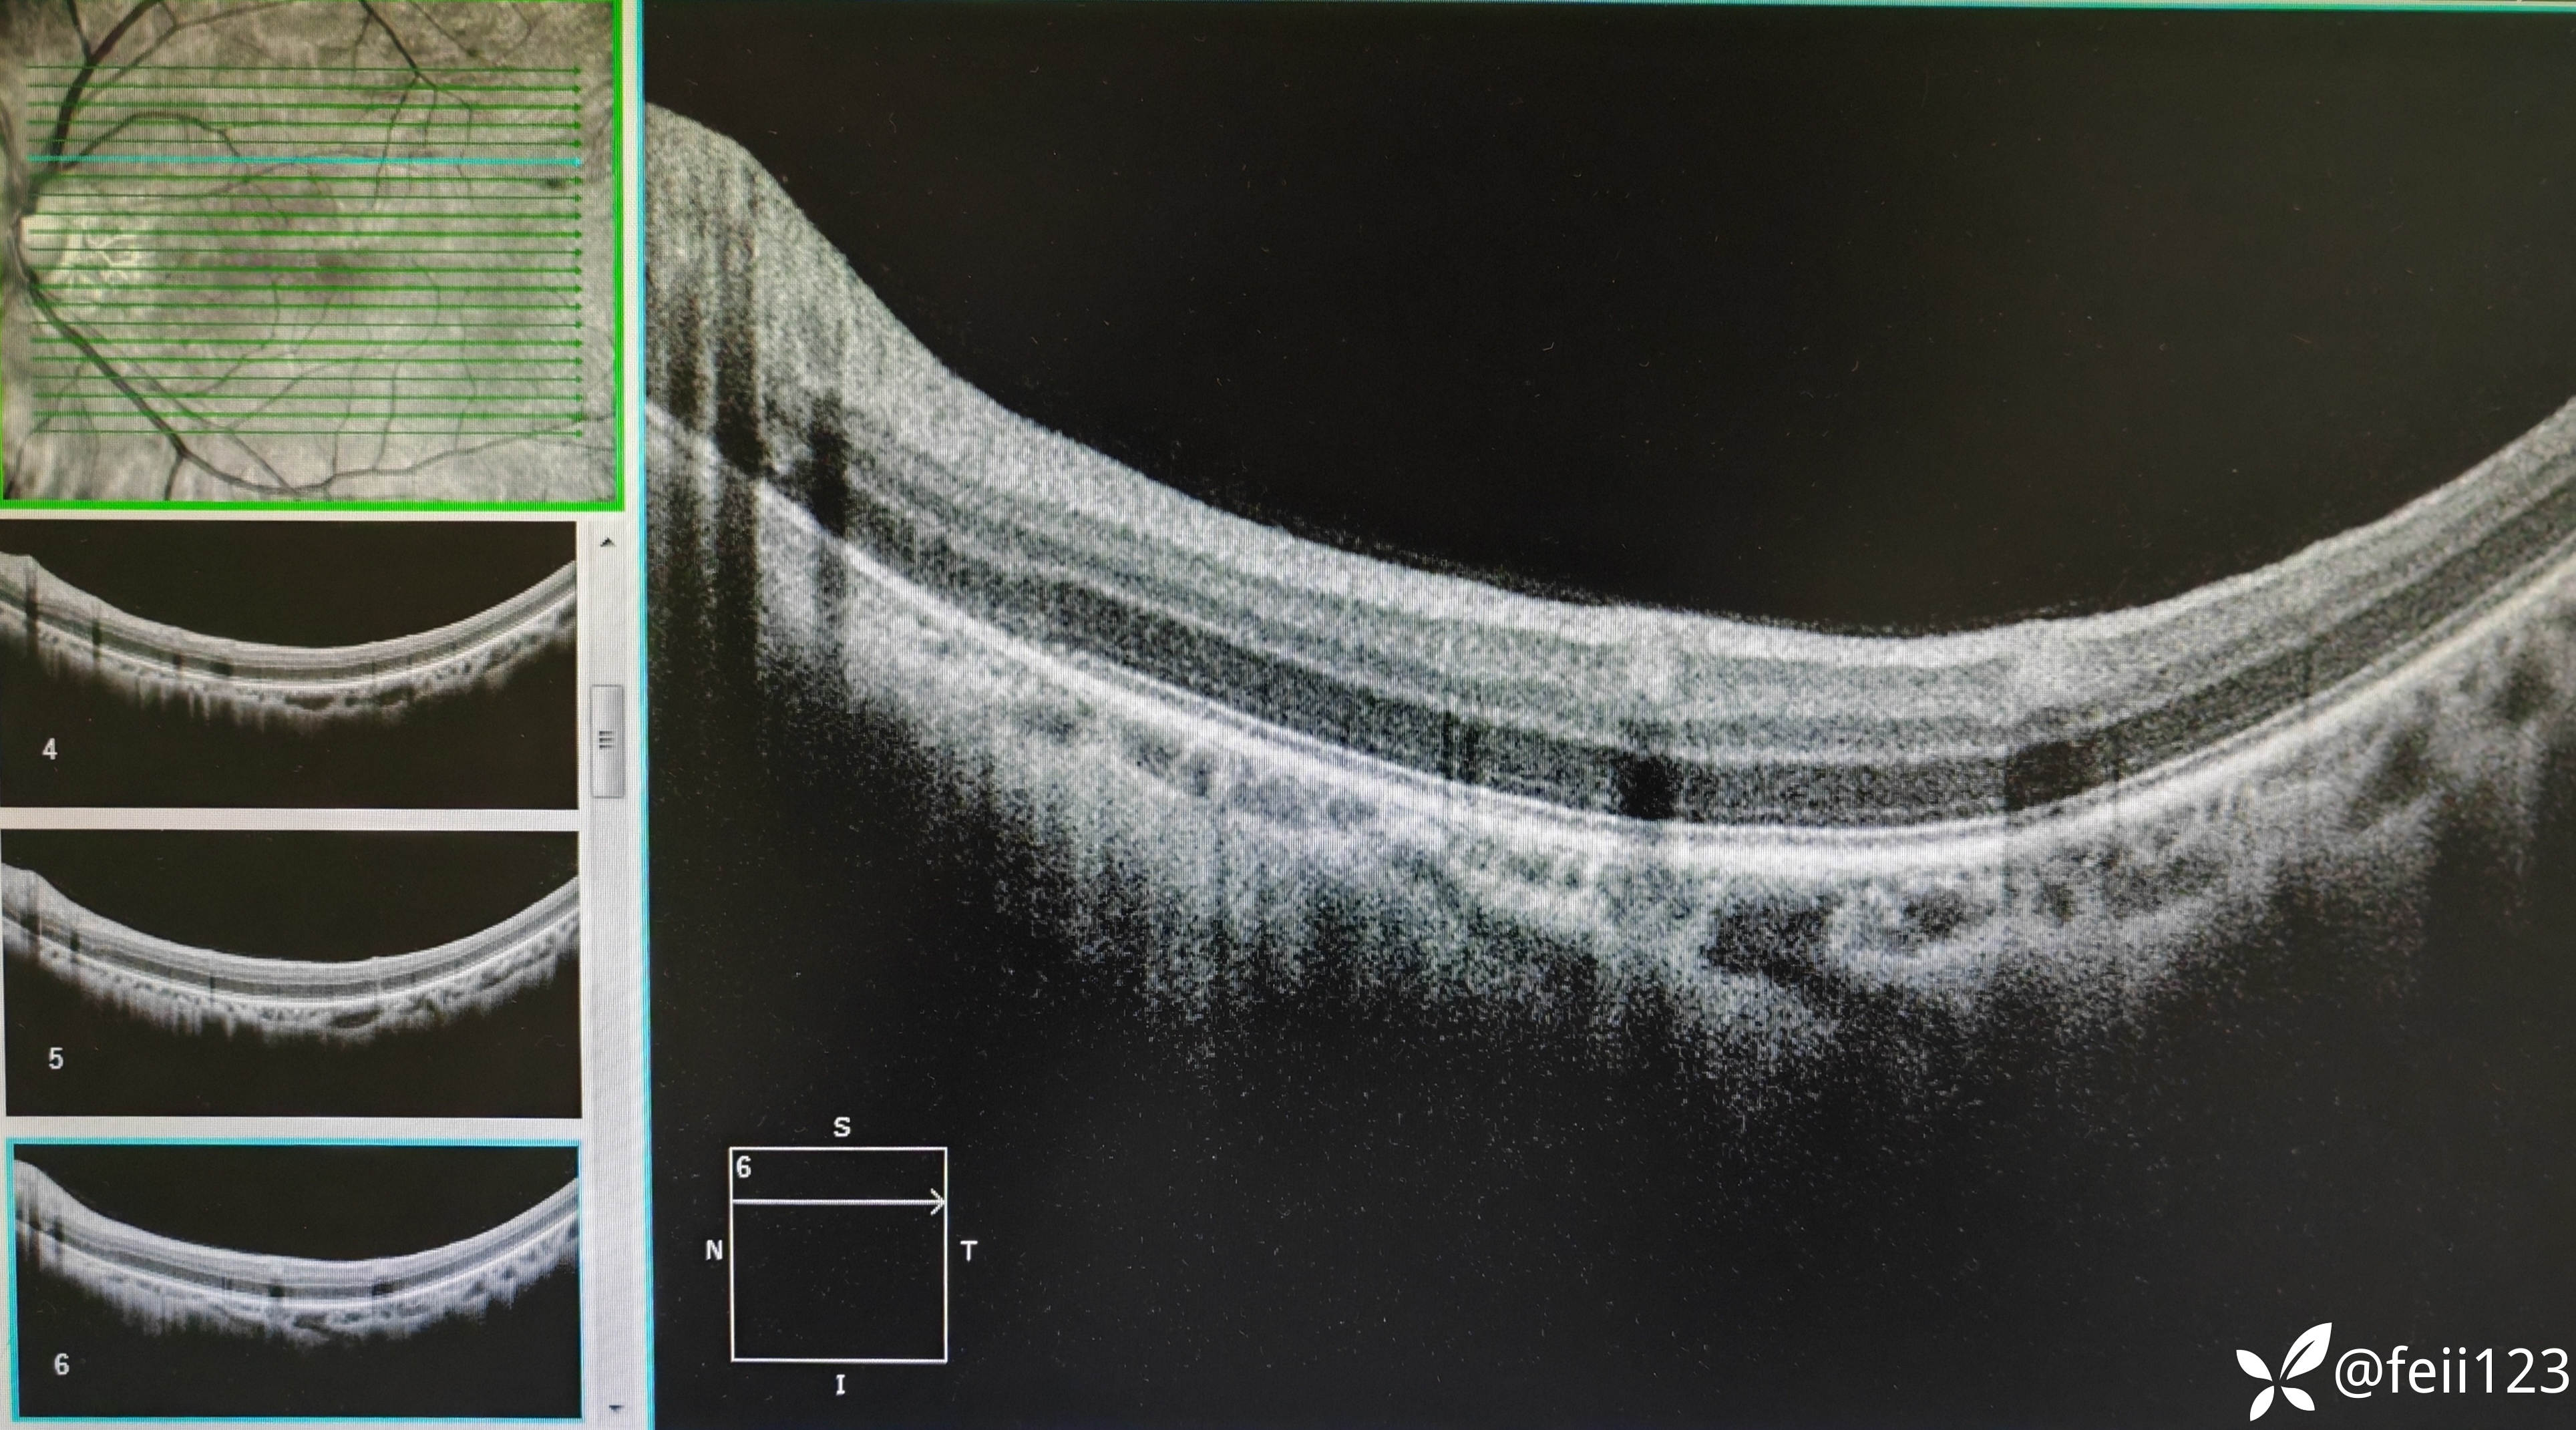

【检查】矫正视力右眼1.0左眼0.4,眼压正常15 16,眼前段未见异常,玻璃体清,眼底如图,左眼底可见后极部及鼻侧周边多个白点。